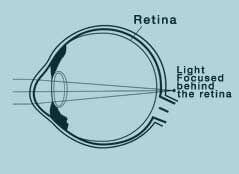

When the focal point is not completely on the retina; that is, when is behind or in front of the retina, the vision is blurred. This is called ametropia, or refractive defiency as publicly known.

Hypermetropia(disability to see objects that are close=far sightedness)

You can see the objects at a distance very clearly whereas you can see the objects close less clearly.

In hypertropia, the patient’s eye grows less than it is supposed to and thus the light beams come together behind the retina.

Unlike myopia, hypertropia in a hypermetropic eye can be balanced by an eye lenses. Eye lenses might be deformed (and as a result of the loss of flexibility) it might enhance the refraction force and that balances the low refraction force of the hypermetropic eye when looked at a distance.

Therefore people suffering from hypermetropia can actually see distant objects very clearly upto a certain age. However, in case of excessive hypermetropia, the use of eyeglasses is suggested even at young ages. Otherwise, the ability to read starts decreasing at an early age; that is to say, presbyopia appears earlier than it is supposed to.

Laser correction is applied in order to increase the refraction force of the optical system. In hypermetropic patients, eye slightly grows and light beams are collected behind the retina.